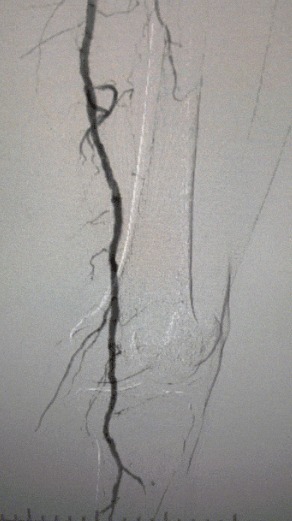

· Imagem pré-operatória: estenose calcificada difusa grave em artérias bilaterais dos membros inferiores

Resultado cirúrgico

Pós-procedimento, a estenose arterial melhorou significativamente, o fluxo sanguíneo aumentou e a temperatura da pele aumentou. Nenhuma complicação pós-operatória ocorreu. Tanto o paciente quanto a equipe cirúrgica ficaram muito satisfeitos com os resultados.